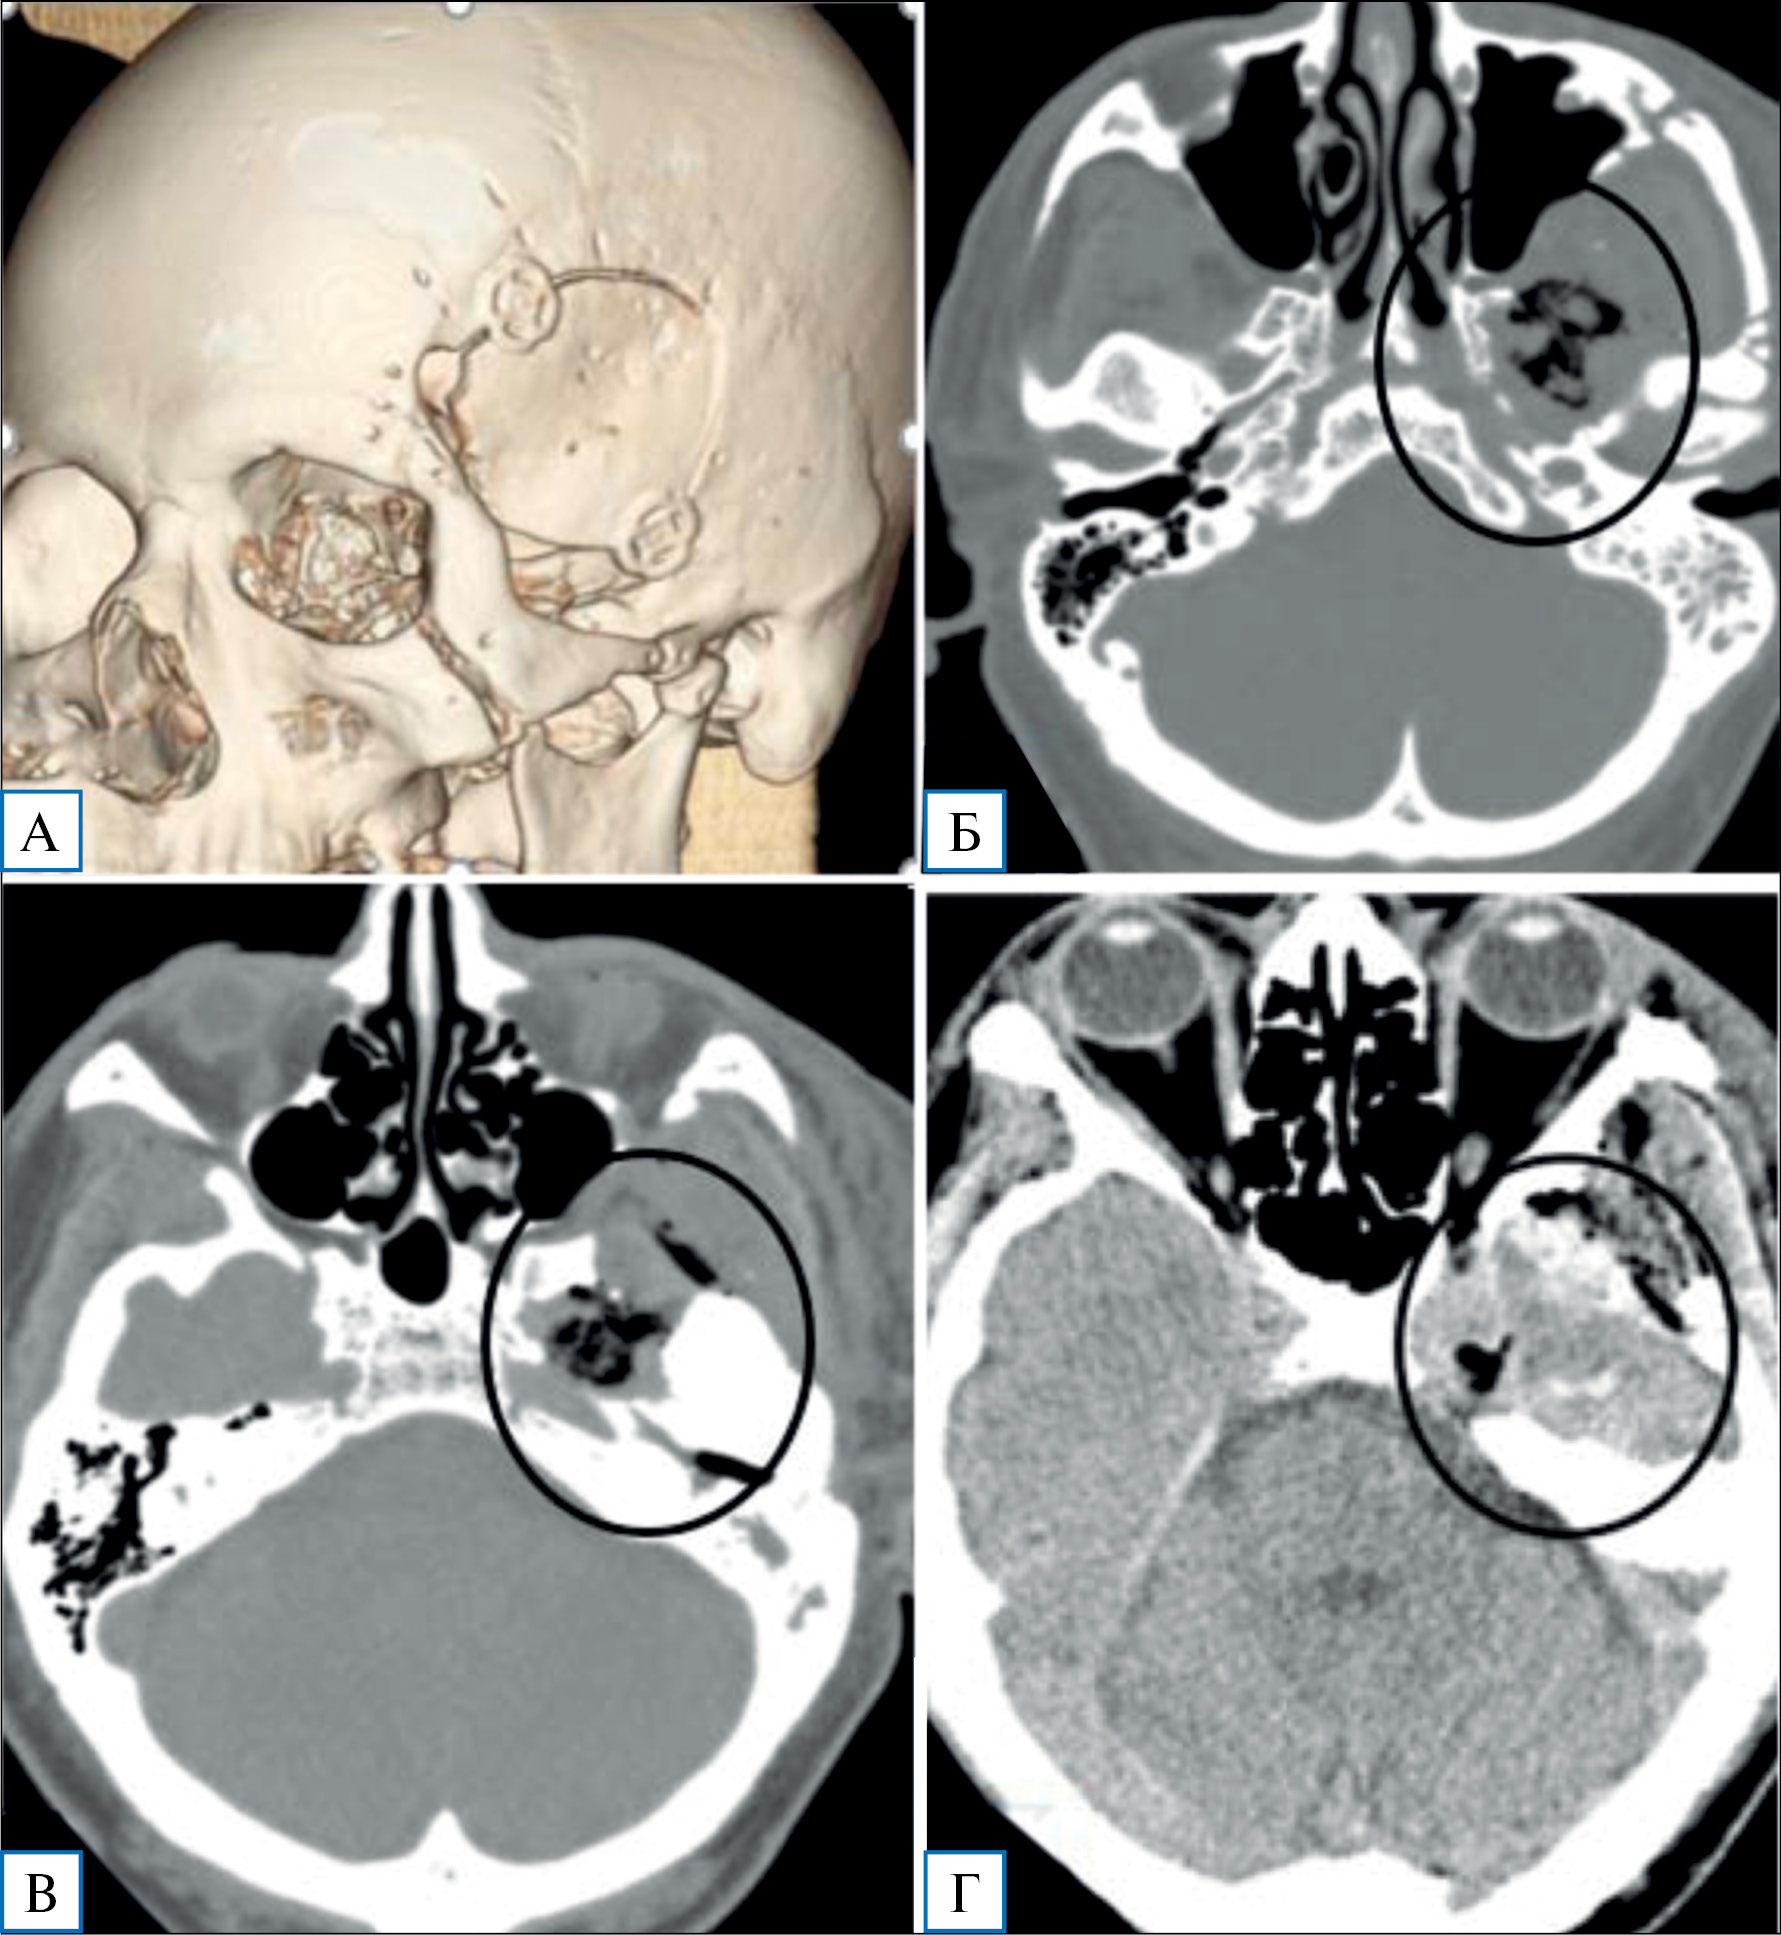

По результатам магнитно-резонансной (МРТ) и компьютерной (КТ) томографии головного мозга с контрастным усилением выявлена невринома левого тройничного нерва по типу «песочных часов». Опухоль локализована от уровня выхода корешка нерва из моста, далее распространяется на основание средней черепной ямки, в подвисочную и левую крылонебную ямки. Общий размер опухоли 5,6 × 4,5 × 2,4 см (рис. 1).

Рис. 1. Пациент М. с невриномой тройничного нерва, 60 лет: магнитно-резонансная томография головного мозга с контрастным усилением

Примечание. На Т2-изображениях определяется невринома тройничного нерва с компрессией ствола головного мозга (А), распространяющаяся в меккелеву полость с компрессией и инвазией кавернозного синуса (В), в подвисочную и крылонебную ямки (Б), вызывающая хронический мастоидит и петрозит (Г).